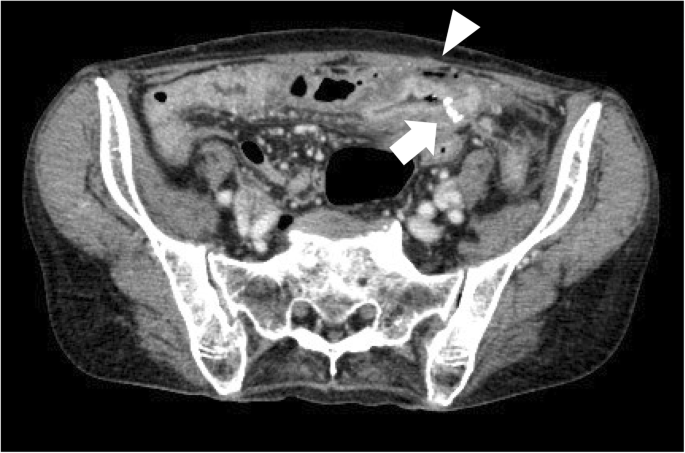

A 62-year-old woman was diagnosed with distal bile duct carcinoma and underwent pylorus-preserving PD with end-to-side duodenojejunostomy using the modified Child method. Ulceration at the duodenum bulb was also identified during the preoperative examination. The postoperative course was uneventful. PPI was prescribed for 7 months and discontinued. Forty-three months after the surgery, she complained of hematochezia, and medical checkup with barium enema was scheduled. She needed to fast for a day before the examination. After the examination, she experienced acute abdominal pain. CT showed intraabdominal free air near the duodenojejunostomy anastomotic site, suggesting marginal ulcer perforation (Fig. 3). As her symptoms were relatively mild, she was treated conservatively with gastric drainage using nasogastric intubation and PPI administration. She was discharged 2 weeks after the admission without complications. She was placed on chronic antisecretory therapy, and to date, no ulcer or cancer recurrence has occurred.